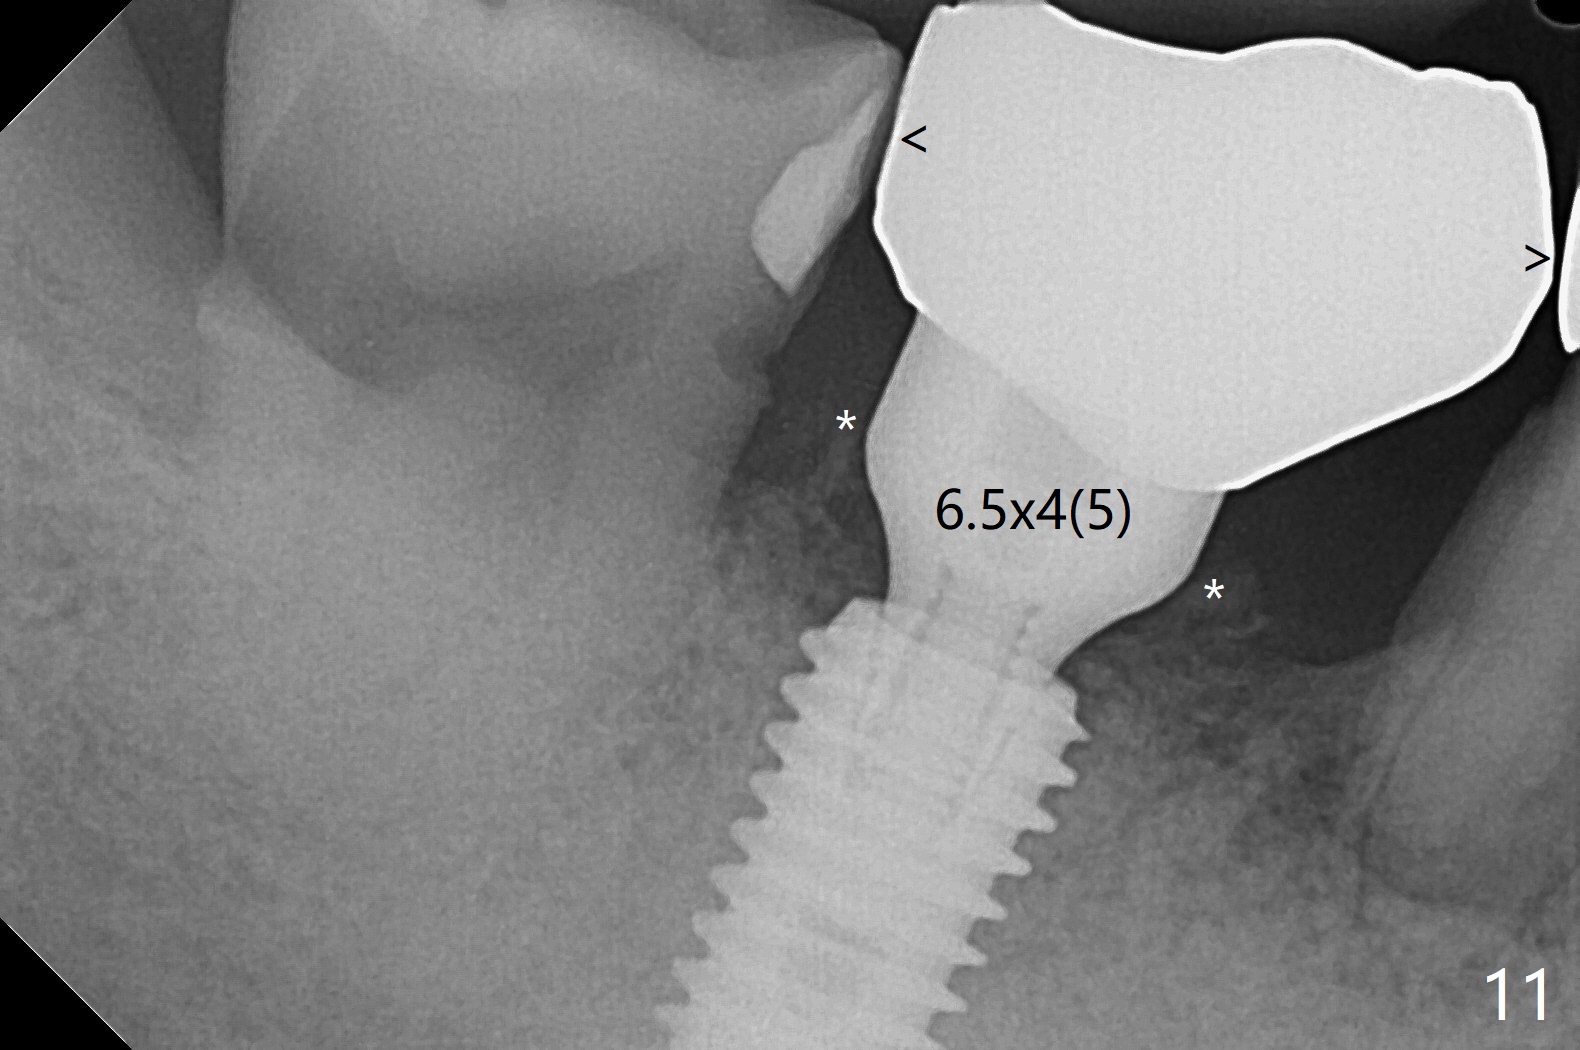

Although the tooth #30 has distobuccal root exposure (Fig.1 <), it is asymptomatic.  In contrast the tooth #31 with the distoocclusal caries (*) is symptomatic.  After use of 2 mm drill for 18 mm (lingual gingival margin), a calculated parallel pin is inserted (Fig.2 (D: 2 distal roots of the tooth #30)).  It appears that a 11.5 mm long implant is appropriate for the site; a 5 mm cuff is expected.  Following 4.8 mm drill, a 5.5x11.5 mm implant is placed initially (Fig.3) with an apical space (*) and clearance from the Inferior Alveolar Canal (red dashed line).  The implant is placed deeper with placement of a 6.5x4(5) mm abutment and bone graft (*, Fig.4,5).  After placement of collagen membrane over the graft, an immediate provisional is fabricated (Fig.6 P) with clearance from the opposing tooth (Fig.7 *).  There is no bone loss 3.5 months postop (Fig.8).  In fact the abutment has not been seated completely since its placement (Fig.4,5,8).  The crown/abutment dislodges 3 years 3 months post cementation (Fig.9).  The latter occurs for long incubation time because of opposing partial denture (Fig.10).  After trimming proximal surfaces (Fig.11: arrowheads), the abutment remains incompletely seated (Fig.11) due to possible crestal bone interference (Fig.11 *).  The smaller abutment by itself remains unseated (Fgi.12).  One size small one is completely seated (Fig.13).  Impression is taken.  Two weeks later the abutment margin is supragingival.  After screw torque at 20 Ncm, the crown is cemented with access hole.  Excess cement is removed.